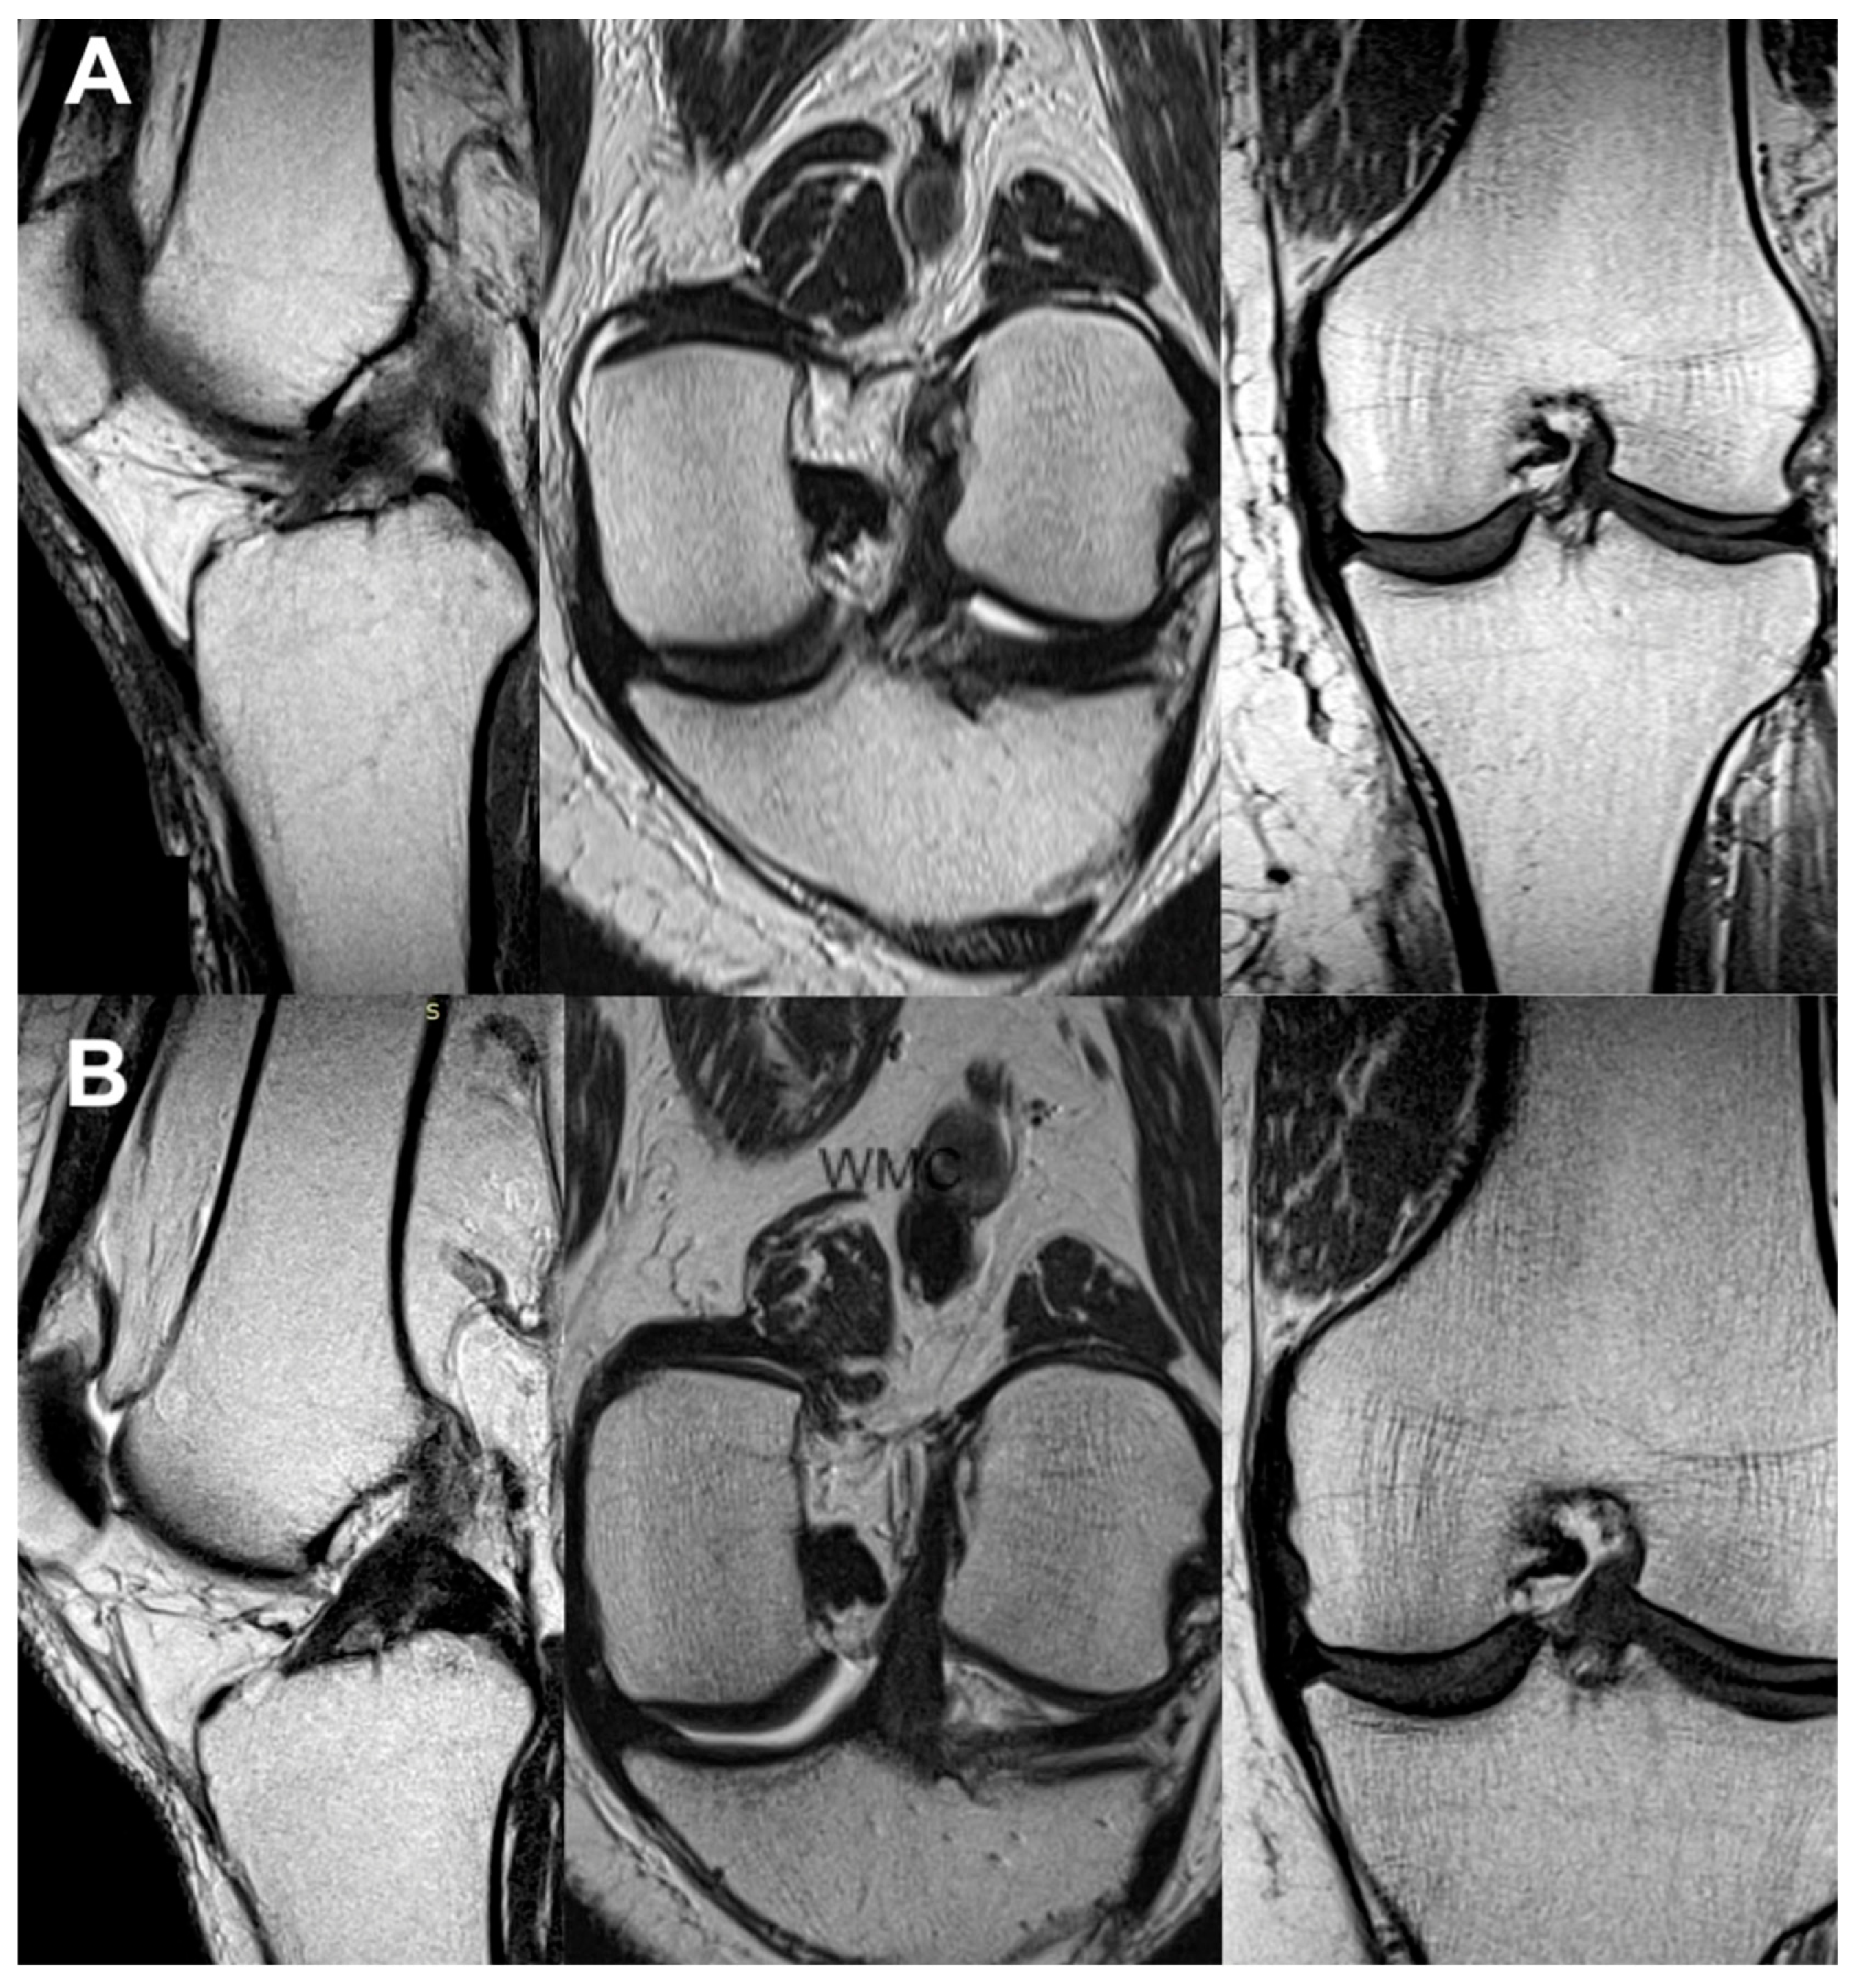

Figure 5.

The same knee MRI scans of a patient with an anterior cruciate ligament tear before treatment (A) and corresponding MRI scans after nanosurgery treatment with an RP-hCM injection (B).